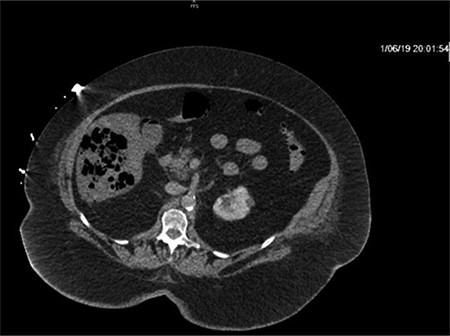

CT of the abdomen and pelvis with IV contrast was performed within 2 h of presentation. The scan showed “indeterminate, scattered ill-defined hypo-enhancing lesions in the liver with no acute etiology identified to explain the patient’s abdominal pain” (Figs 1, 3, 5). The remainder of the CT was unremarkable. Ultrasound (US) of the abdomen was negative. Because the CT and US did not identify an etiology for the patient’s abdominal pain, the working diagnosis at that time was an intestinal obstructive process.

CT with IV contrast taken at 0633 which shows ill defined, hypo-enhanced lesions of the liver.

Repeat CT demonstrated a large amount of air within the liver parenchyma (Figs 2, 4, 6). Unfortunately, shortly after the repeat CT, the patient progressed to septic shock with cardiovascular collapse and was not able to be resuscitated with full advanced cardiac life support (ACLS) protocol. She expired within 16 h of initial presentation and within 24 h of symptom onset. Final blood culture results were positive for Clostridium perfringens.

Repeat imaging taken 13.5 h later which depicts many air bubbles in the liver parenchyma.